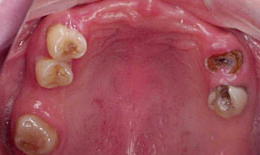

インプラント症例(1)30代 女性

治療前

上顎

保存困難な歯を抜歯後、インプラントを7本埋め込み、セラミックスクラウンを被せた

下顎

保存困難な歯を抜歯後、インプラントを6本埋め込み、セラミックスクラウンを被せた